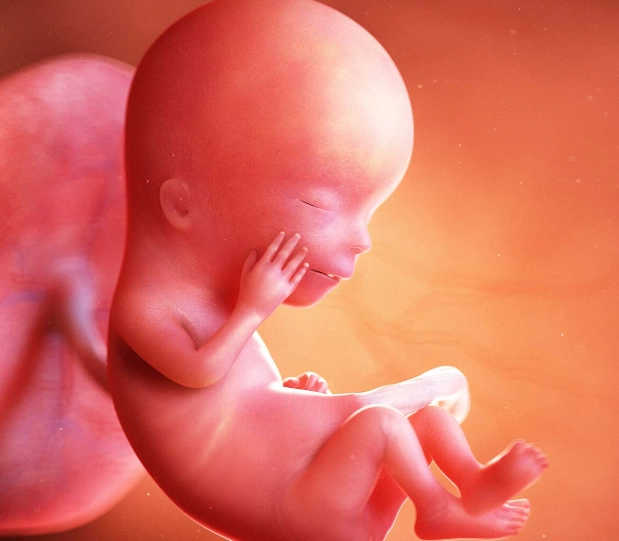

Okay, so you're three months pregnant. What does your baby look like now? This is where it gets exciting. By 12 weeks, the embryo is now officially called a fetus. The basic structure for everything is there—it's all about refinement and growth from here on out.

According to resources from the American College of Obstetricians and Gynecologists (ACOG), the fetus is now about the size of a lime or a plum, roughly 2.5 inches long from crown to rump, and may weigh around half an ounce.

But size is the least interesting part. Here’s what’s developing:

Major Organ Systems are Up and Running

The hard work of the first trimester is mostly done. The brain, spinal cord, heart, kidneys, liver, and intestines have all formed and are starting to function. The heart is beating at a crazy rate of about 150-180 beats per minute—you might even hear it at your next ultrasound!

Bones are beginning to harden (ossify), starting with the skull and long bones. Tiny fingernails and toenails are forming. The intestines, which started out in the umbilical cord, are now moving into the abdominal cavity where they belong.

Looks More Like a Baby

The face is becoming more defined. The eyes, which started on the sides of the head, have moved closer together. The ears are now in their final position on the sides of the head. The mouth can open and close, and the baby might even start practicing sucking motions. All twenty baby teeth buds are in place under the gums.

Perhaps most amazingly, the baby is moving! A lot. Kicking, stretching, even doing somersaults. You won't feel these acrobatics for several more weeks, but if you have an ultrasound around this time, you might get a show.

Fun Fact: At 12 weeks, the fetus's reflexes are kicking in. If you were to poke your belly (not that you could feel it from the outside), the baby might squirm in response. The hands can make fists, and the feet may curl.